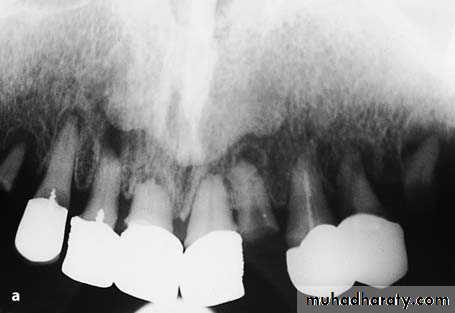

preprosthatic surgery

a Radiograph of maxillary teeth, after whose removal smoothing of alveolar bone is required. b Clinical photograph of teeth to be extracted

Diagrammatic illustration (a) and clinical photograph (b) of gross intraseptal irregularities after multiple tooth extractions